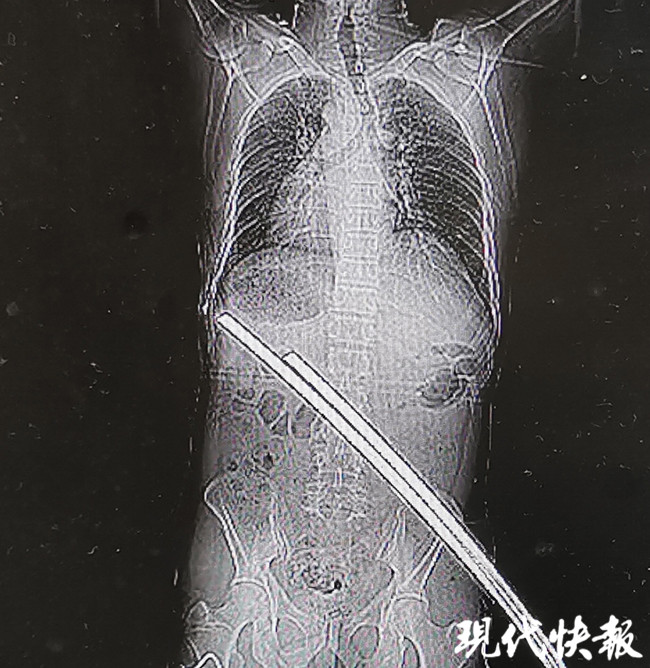

△兩根鋼筋刺穿張師傅腰部

當(dāng)天,55歲的水電工張師傅(化名)正在17樓高空作業(yè),他踩在一塊懸空搭建的木板上,不料木板突然斷裂,張師傅瞬間下墜,當(dāng)其墜落至15樓時,兩根鋼筋“接”住了他,從其臀部向腰部斜行刺穿。

△刺穿張師傅身體的兩根鋼筋

通過CT檢查,醫(yī)生稱鋼筋只是刺穿張師傅的肌肉,萬幸的是并未累及身體重要臟器和血管,除此以外,張師傅肋骨骨折、左肘部皮膚擦傷,無生命危險(xiǎn)。經(jīng)過兩個小時的急診手術(shù),鋼筋從張師傅右臀部被拔除,手術(shù)一切順利。